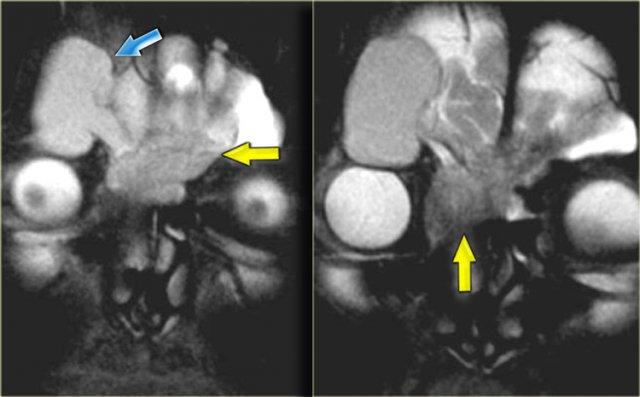

Hình ảnh bên trái của một bệnh nhân bị viêm xoang cấp tính và bệnh lý tế bào khí sàng.

Bệnh nhân nhập viện với triệu chứng nhìn mờ.

Chú ý dịch trong mỏm yên trước trái.

Dây thần kinh thị giác chạy ở phía trong của nó.

Tiếp tục xem các hình ảnh mặt phẳng coronal.

Chuỗi xung T2W mặt phẳng coronal cho thấy sự giãn rộng của mỏm yên.

Chuỗi xung T1W cho thấy mất tín hiệu mỡ bình thường so với bên phải, và lan rộng vào đỉnh hốc mắt (mũi tên đỏ).

Đây là nang nhầy của mỏm yên trước với tổn thương thứ phát dây thần kinh thị giác.